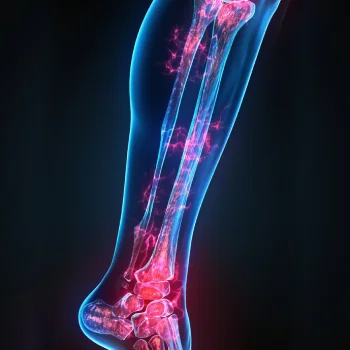

در این روش تصویر برداری یک صفحه (گیرنده یا دتکتور) در زیر عضو و قسمت مورد نظر قرار داده می شود و اشعه ایکس(دُز از اشعه جهت تشخیص) به همان قسمت که روی صفحه قرار گرفته تابنده می شود و توسط صفحه اطلاعات دریافت می شوند و همین اطلاعات پس از پردازش های لازم در نهایت عکس رادیولوژی به ما ارائه می دهد. کاربردهای رادیولوژی در منزل دقیقاً همان کاربرد رادیولوژی در بیمارستان ها می باشد از جمله بررسی انواع شکستگی ها، دررفتگی مفاصل، آرتروز مفاصل، دیدن پروتز های داخل استخوان از نظر بررسی موقعیت پروتز، آب آوردگی ریه(اِدم وافیوژن) و عفونت ریه، شکستگی دنده ها، انساد و وجود هوا در شکم و… می باشند. رادیولوژی در منزل تمام این خدمات را ارائه می دهد.

تصاویری از رادیولوژی در منزل توسط گاما پرتو